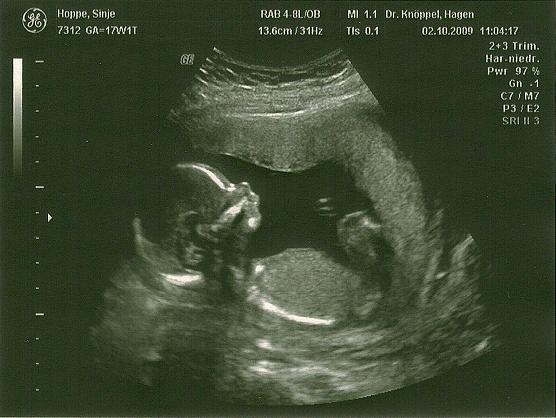

Hallo ich bin wieder zurück von der VU. War alles super Ausgangsgewicht + 1 kg, Blutdruck 110/70 und Urin und Abstrich auch super. Der US war auch toll haben sigar schon nen 3D Bild gemacht... Und der Krümel liegt in BEL. Naja aber zeigen wollte er/sie sich nicht :( grml. Mein Mann nd ich haben doch ne Wette laufen. Er hat gesucht und gesucht aber es hatte immer schön die Beine, Nabelschnur und Füße davor.... Da konnteman nix machen wirhaben 10 min. gesucht.... Mensch naja wieder 4 Wochen warten:(

Ich finde 3D-Bilder irgendwie immer etwas gruselig.... aber toll sind beide, süßes Gesichtchen! Was ich aber nicht verstehe - in exakt dieser Haltung lag mein Zwerg vor zwei Tagen auch und der Arzt hat dann einfach nur die Tiefenschärfe etwas verändert, so dass wir zwischen den Beinen gelandet sind und beste Sicht hatten ;-) Man muss doch nicht zwingend von vorne draufgucken *wunder*? Hängt aber vielleicht vom US-Gerät ab? Hm....

Sehr schöne Bilder Ich finde ja das Kleine sieht aus wie ein Junge Aber wer weiß

Mensch, schade, dass es sich nicht geoutet hat. Finde aber auch, dass es nach Junge aussieht!!